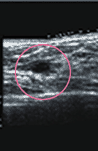

| マンモグラフィ検査 | 超音波検査 | MRI検査・CT検査 |